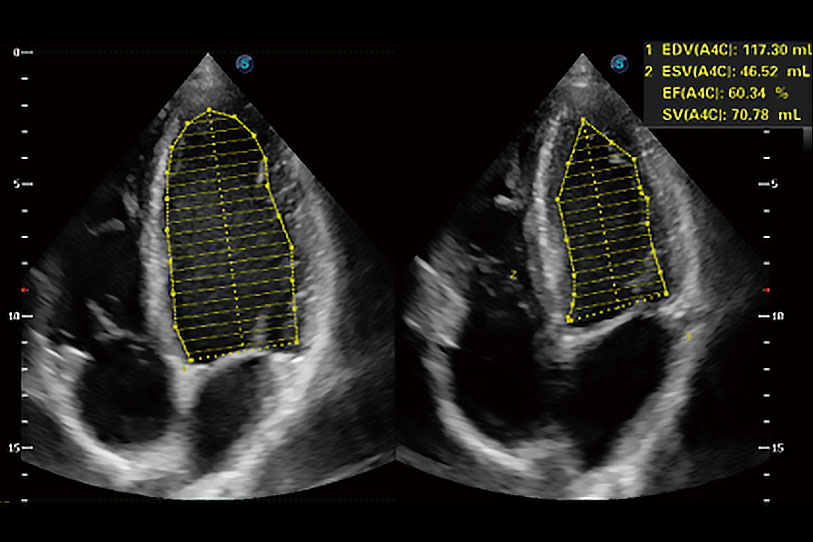

能夠基于左心室壁追蹤和辛普森法,自動(dòng)計(jì)算射血分?jǐn)?shù),支持多個(gè)可移動(dòng)點(diǎn)描跡,與手動(dòng)測量相比,極大節(jié)省了動(dòng)物醫(yī)生的時(shí)間和精力。